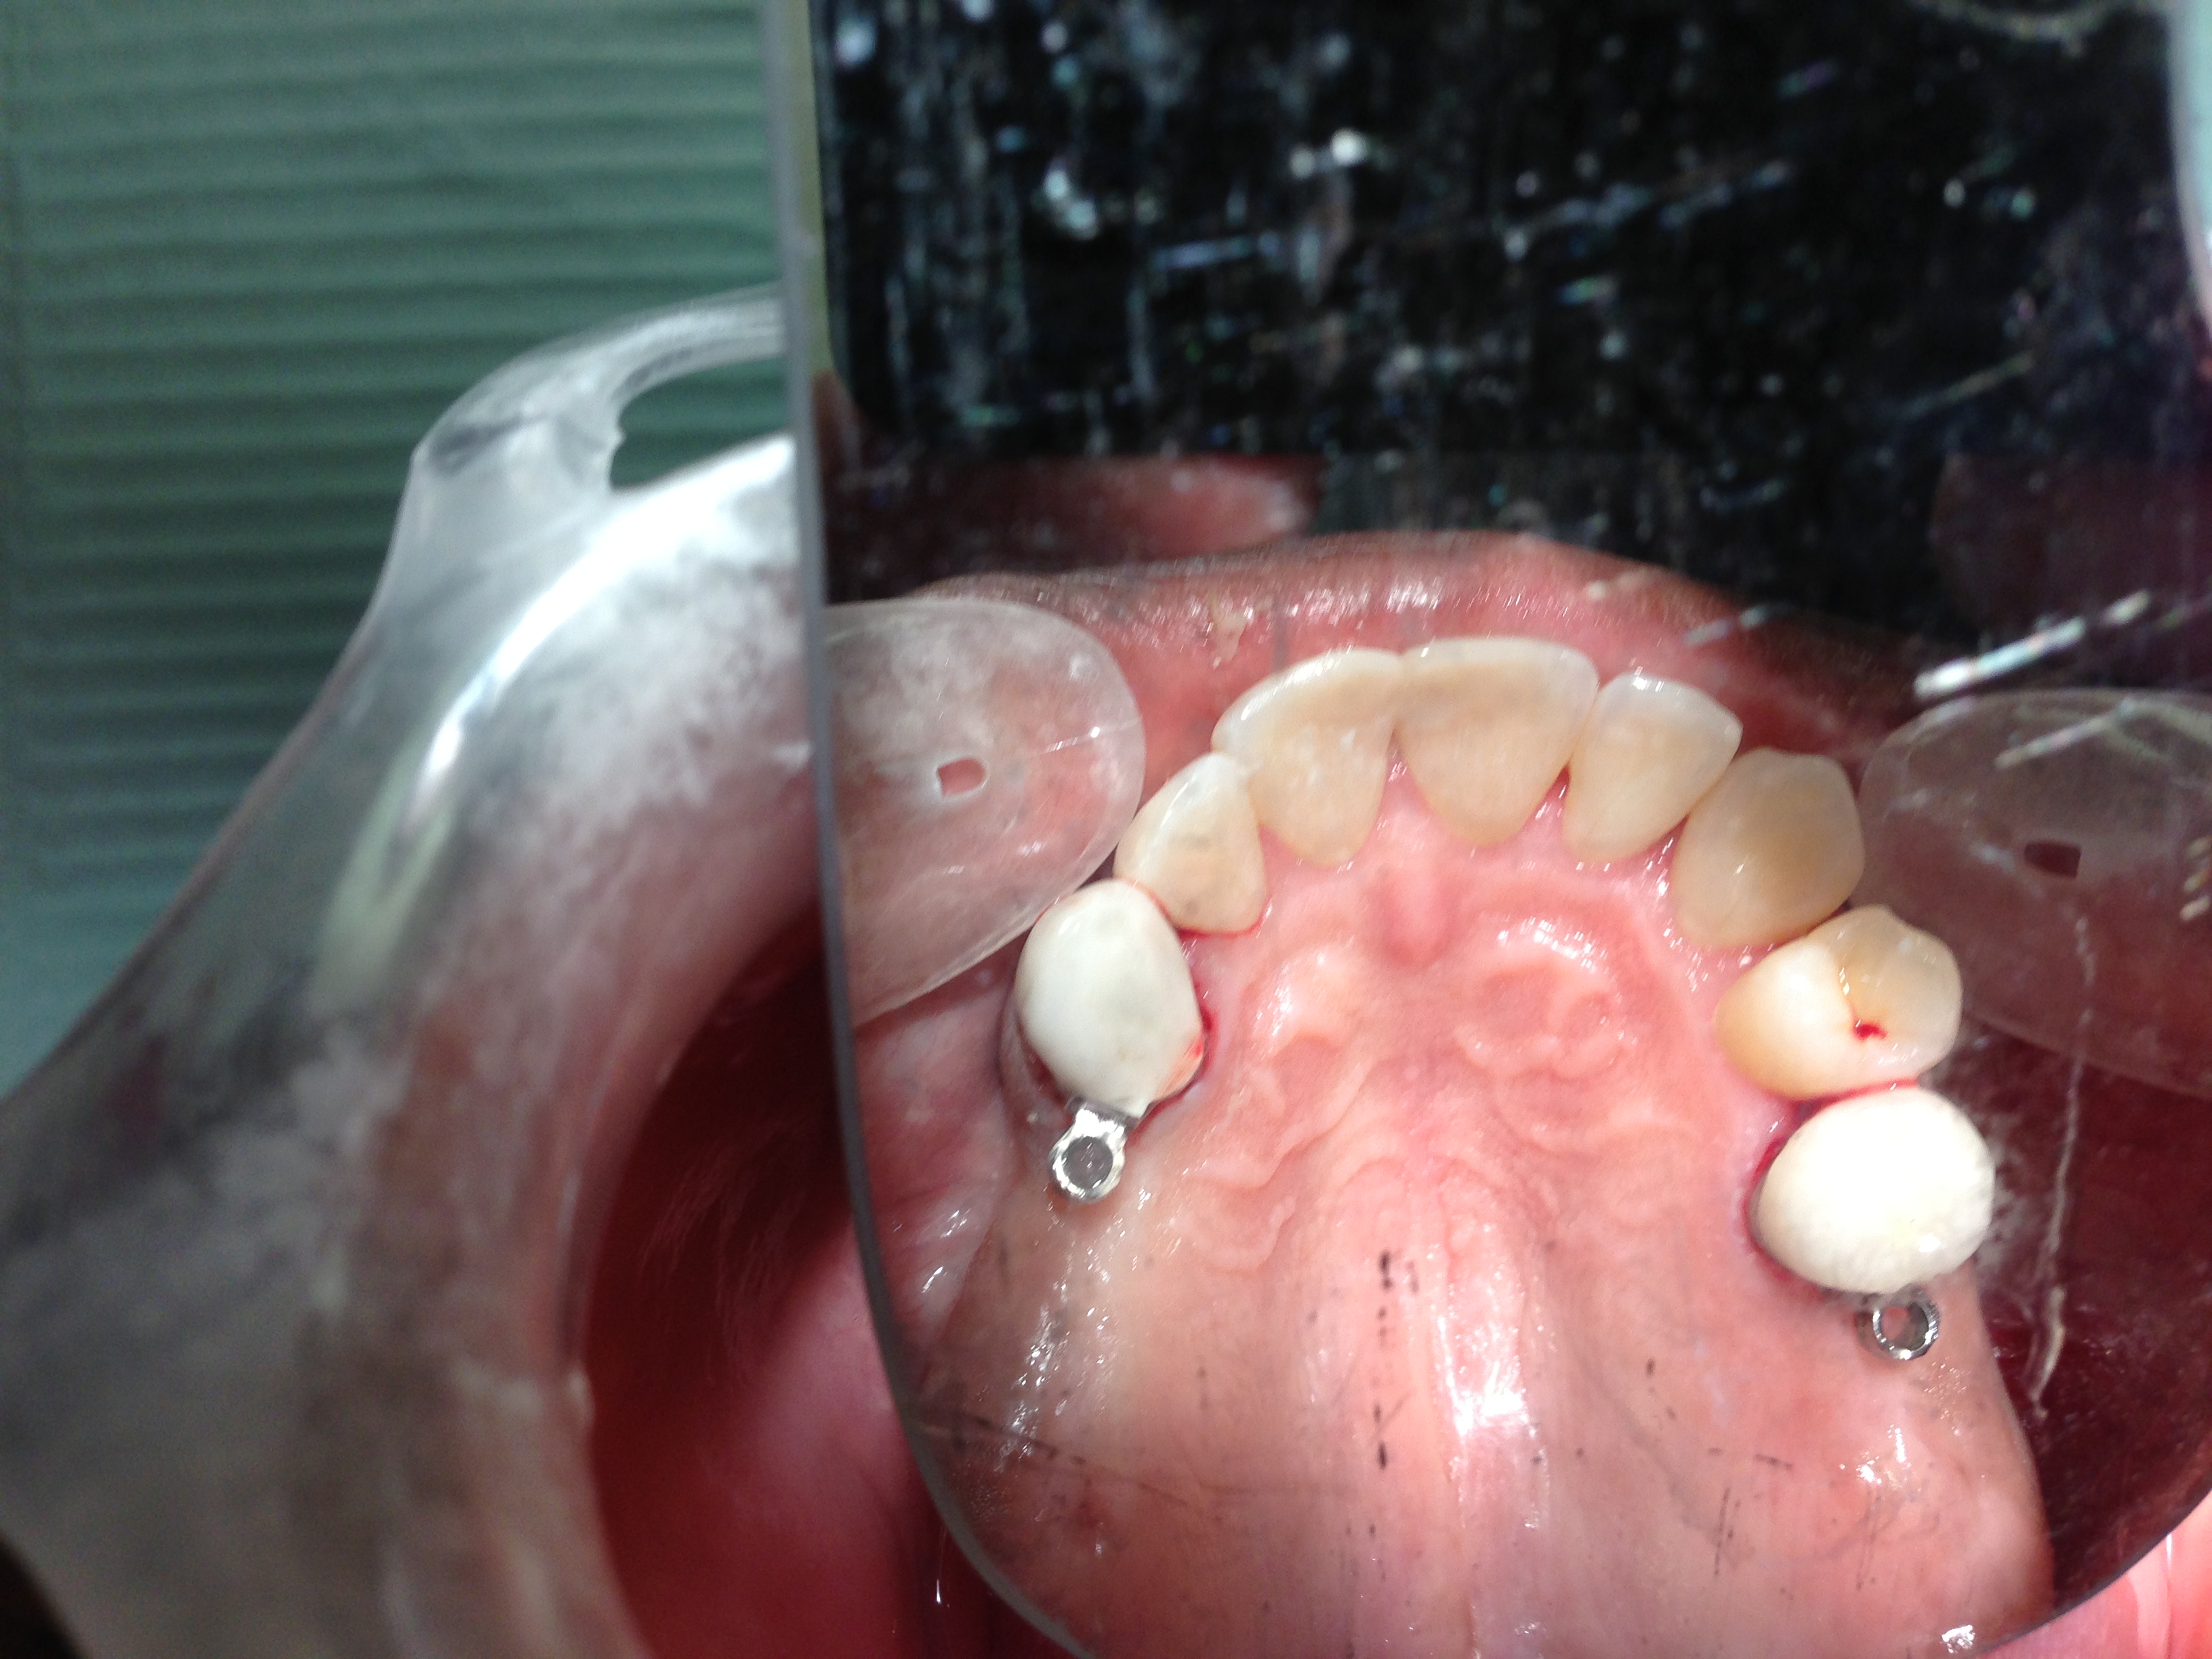

Yes, a partial can be made without clasp, if the teeth adjacent to the space have crowns made with rings on them call ERA attachments. This allows a great smile without the metal clasp seen with many partial dentures.